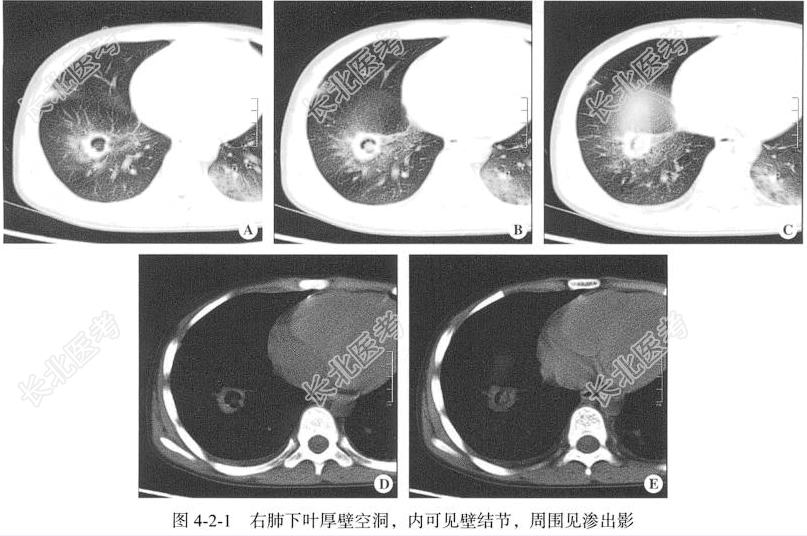

【胸部CT检查】仰卧位,横断位扫描,行胸部扫描,扫描范围自胸廓入口水平至膈肌水平,扫描层厚为2mm,层间隔2mm,行局部高分辨扫描。

【影像图片】见图4-2-1。